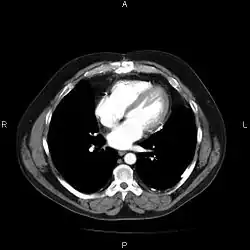

An image as stored on a picture archiving and communication system (PACS)

A chest image displayed via a PACS

A full PACS should provide a single point of access for images and their associated data. That is, it should support all digital modalities, in all departments, throughout the organisation.